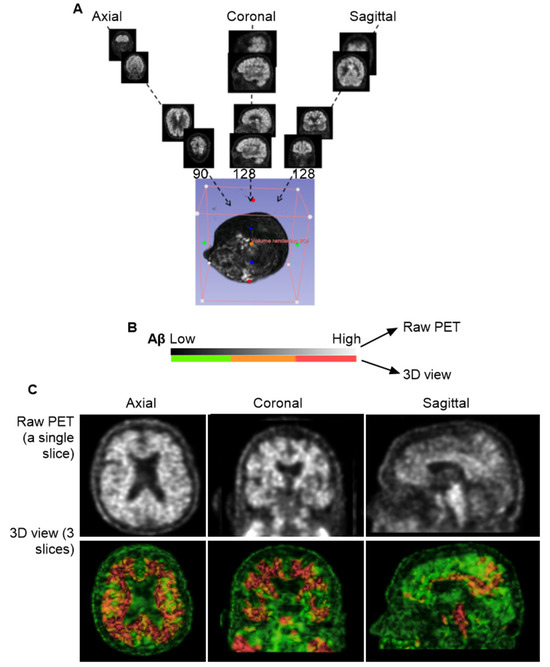

The individual slice thickness in florbetapir PET scans is 2.0 mm, displaying as gray signals against the black background. At this resolution, the intensity of Aβ signals is often low and appears blurred to the human eye. To improve the analysis of the Aβ signal, we reconstructed these slices into a 3D volumetric image, enabling to gather more signals from regions of interest (ROIs) across multiple spatial dimensions. Figure 1A illustrates the transformation from 2D slices to a compact 3D volume encompassing the brain, skull, and portions of the cervical region. However, this initial 3D reconstruction was suboptimal for analysis and required further processing.

In the original PET images, Aβ concentrations were represented by grayscale pixel values ranging from 0 (black; no Aβ) to 255 (white; highest Aβ concentration). Following 3D reconstruction, these 2D pixels were converted into 3D voxels, each assigned to a color based on an arbitrary intensity scale (Figure 1B). In this study, voxel intensities were visualized using a color gradient: green for the lowest Aβ levels, yellow to brown for intermediate levels, and red for the highest concentrations.

To refine the imaging, we applied convolutional neural networks (CNNs) to filter out noise associated with positron straying far from radioligand binding sites, while enhancing signals proximal to ligand interactions. This CNN-based process significantly improved image clarity and reduced blurring. We found that using three consecutive slices was sufficient to produce a clear and interpretable image (Figure 1C). However, when more than ten slices were combined, the resulting visualization became overly complex, obscuring individual anatomical features. Interestingly, Aβ signals were detected not only within the brain parenchyma but also in peripheral regions, including the skull and cervical areas. Notably, Aβ concentrations appeared homogeneous in the skull but heterogeneous in the cervical region, suggesting a broader anatomical distribution and potentially dynamic clearance pathways beyond the central nervous system.

Figure 1. Three-dimensional Reconstruction for Florbetapir PET Imaging. (A), General workflow for generating a 3D volume from PET data. A total of 346 individual slices were synthesized into a single 3D image. The imaging data were obtained from the CU-1 individual (see Table 1 in Section 2) and used here as a representative demonstration. (B), Voxel-based color mapping of Aβ concentration following 3D reconstruction. Original PET grayscale values (ranging from 0 [black; no Aβ] to 255 [bright; highest Aβ]) were converted into voxel intensities and visualized using a color gradient: green () for the lowest Aβ levels, yellow-brown for intermediate levels (), and red for the highest concentrations (). (C), Comparison between raw PET imaging (top panel) and 3D reconstruction (bottom panel). The 3D reconstruction significantly improved image clarity, with optimal visualization achieved using three slices of 6.0 mm thickness.